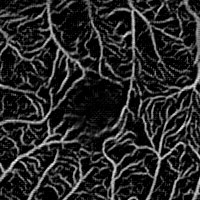

Fig. 4 shows a qualitative ablation study: it illustrates that the intensity representation may miss large vessels in the very high-resolution HRF images, while remains robust. In contrast, provides sharper delineation for very thin vessels in ROSE. The fusion of both pathways outperforms either pathway for most scenarios. These observations are further supported by the quantitative ablation study in Fig.6. We note that and can be used as synthetic angiograms that provide both enhanced vessel visualization and model interpretability.

Fig. 5 shows the t-SNE plots [20] of the datasets. The distribution gaps between datasets are greatly reduced for the two latent vessel representations.